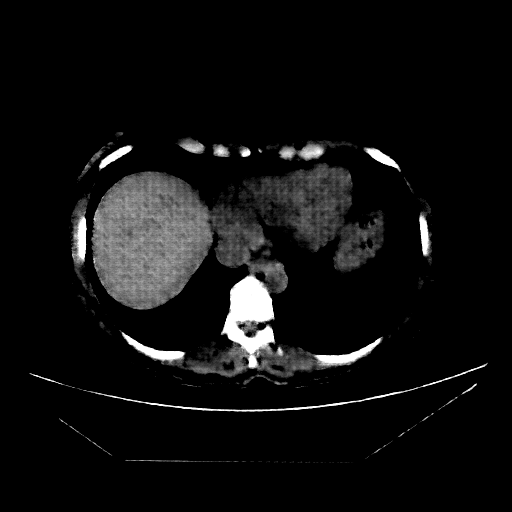

Generated VENOUS CT scan (A→B translation)

Full window (WL 1023.5, WW 4095 β†’ Low βˆ’1024, High +3071)

Lung window (WL -600, WW 1500 β†’ Low βˆ’1350, High +150)

Mediastinum window (WL 40, WW 400 β†’ Low βˆ’160, High +240)